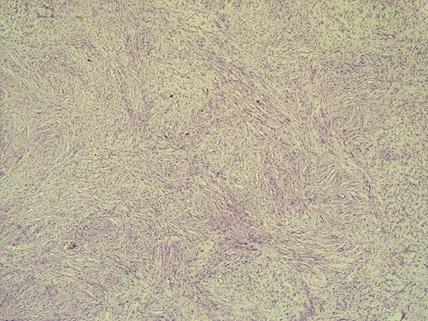

* Case 10: Dr Nathan McGrath (University of the Witwatersrand)

email: nathmcg@gmail.com

Clinical detail: A 53-year-old female, para 2 gravida 2, was referred to the gynecology department at CHBAH with seven years history of menorrhagia, dysmenorrhea, and symptomatic iron deficiency anemia.  The patient had an enlarged, irregular uterus and a transvaginal ultrasound examination showed multiple solid hypo-echoic intramural and subserosal masses, in keeping with a multifibroid uterus. Due to persistent symptoms, an elective total abdominal hysterectomy was performed.